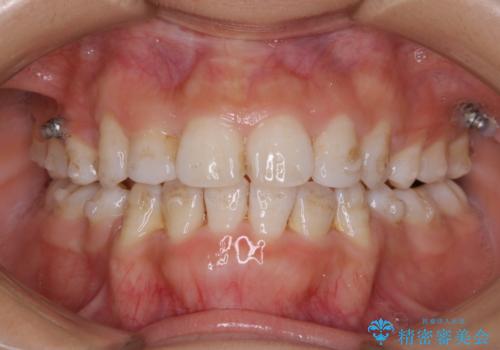

歯の着色だけでなく、汚れもとれ歯の表面がツルツルになったと

喜んでいただけました。

- 歯を白くする目的の施術ではありません